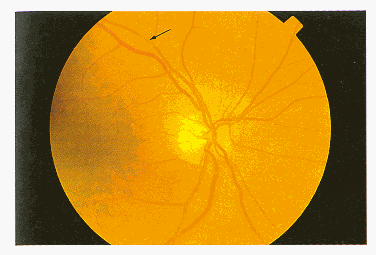

Grado IV: l’arteriola diventa molto sottile ed ha l’aspetto di un cordone fibroso (figura 9).

Figura 9 Restringimento generalizzato. (a) normale. rapporto A/V > 3/4; (b) grado II: rapporto A/V compreso tra 1/2 e 1/3; (c) grado III: rapporto A/V compreso fra 1/3 e 1/4.